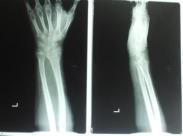

橈骨莖突骨折多為跌倒時手掌著地,暴力沿腕舟骨沖擊橈骨下端;或用手搖汽車發動機,被翻轉的搖手柄擊傷橈骨莖突部所致的骨折,故也有搖手柄骨折之稱。骨折線常呈橫形,波及橈腕關節,骨折塊多無移位。